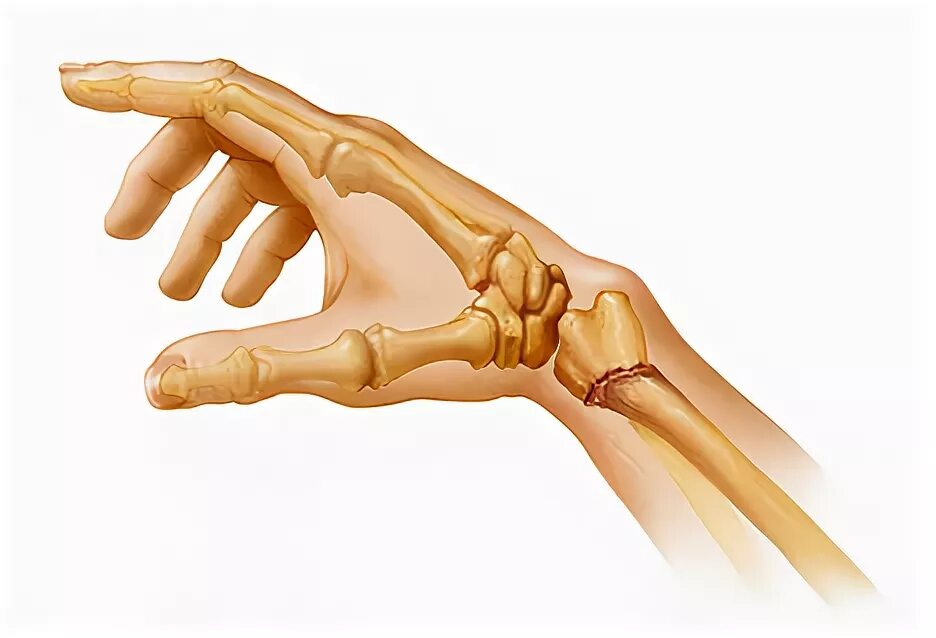

Ушиб лучезапястного